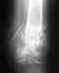

Беспокоило или не беспокоило Вас что-то в предыдущие 10 мес. - уже не важно, на сегодня очевидно, что конструкция разрушена, а сращения нет.

Как назвать эту ситуацию - несращение, ложный сустав - непринципиально.

Варианты лечения возможны все: и накостный остеосинтез с костной пластикой, и остеосинтез по Илизарову, и замена на другой штифт. Гипсовая повязка скорее приведет к потере движений в локтевом суставе, чем к сращению.